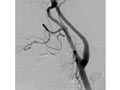

Further tests are often done to identify the cause of the TIA. If blockage of the carotid arteries is suspected, you may have tests such as:

In this procedure, a doctor threads a thin tube called a catheter through an artery in the groin and up to the carotid artery in your neck. The doctor then uses a tiny balloon to enlarge the narrowed portion of the artery and places a stent to keep the artery open.